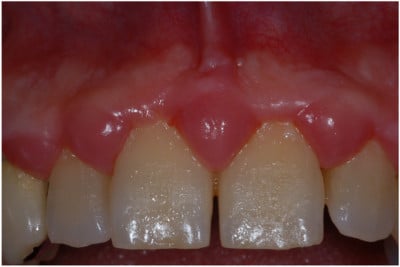

La gengiva sana è di colore rosa pallido uniforme con spessore consistente che si estende armoniosamente e a forma di lama di coltello attorno agli elementi dentari insinuandosi fra questi con papille appuntite di forma piramidale.

In presenza di placca batterica, presenza indotta e causata da un non corretto spazzolamento, avviene un’alterazione funzionale ed estetica sia nel colore che nell’aspetto e forma della gengiva, specie quella marginale attorno ai denti. In altre parole, ha luogo un’infiammazione, che spesso porta dolore alle gengive.

La gengiva passa inizialmente ad un colore rossiccio poi rosso vivo, acceso, cambiando il suo profilo marginale di lama di coltello a quello di rullo aumentando di volume (gengiva gonfia) e diventando edematosa ed iperemica, sensibilissima al sanguinamento.

Le papille in questa fase appaiono rigonfie, debordano dallo spazio interdentale e alla pressione presentano un fluido biancastro denominato essudato.

I denti in questa fase cambiano di colore, da bianco a giallo marrone, ricoprendosi di materia alba e placca batterica, perdono la loro luminosità contribuendo all’inestetismo orale.